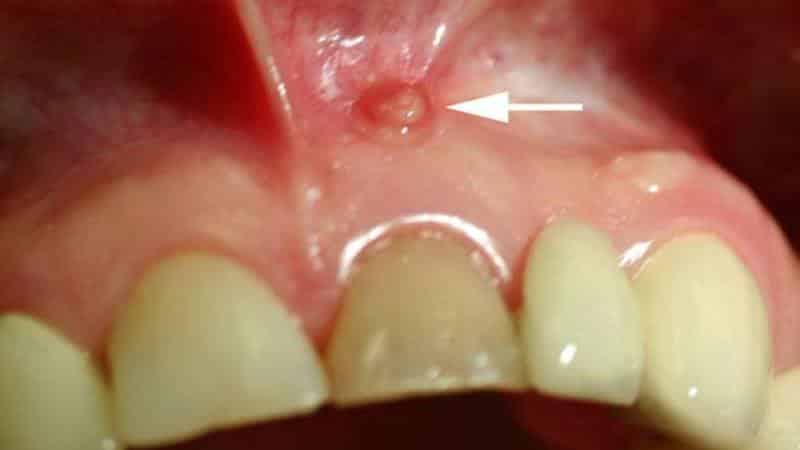

Свищ на десне

Свищ на десне – это гнойное заболевание, сопровождающееся воспалительным процессом. Он представляет собой канал, который соединяет воспалительный очаг с внешней поверхностью.

На десне у основания зуба может образоваться гнойный пузырь, появление которого связано с внутренним нагноением.

Если у вас появился свищ на десне, важно обратиться к врачу. Специалист проведет необходимое лечение, направленное на устранение источника инфекции. В результате гной перестанет выделяться, и пораженная область заживет.